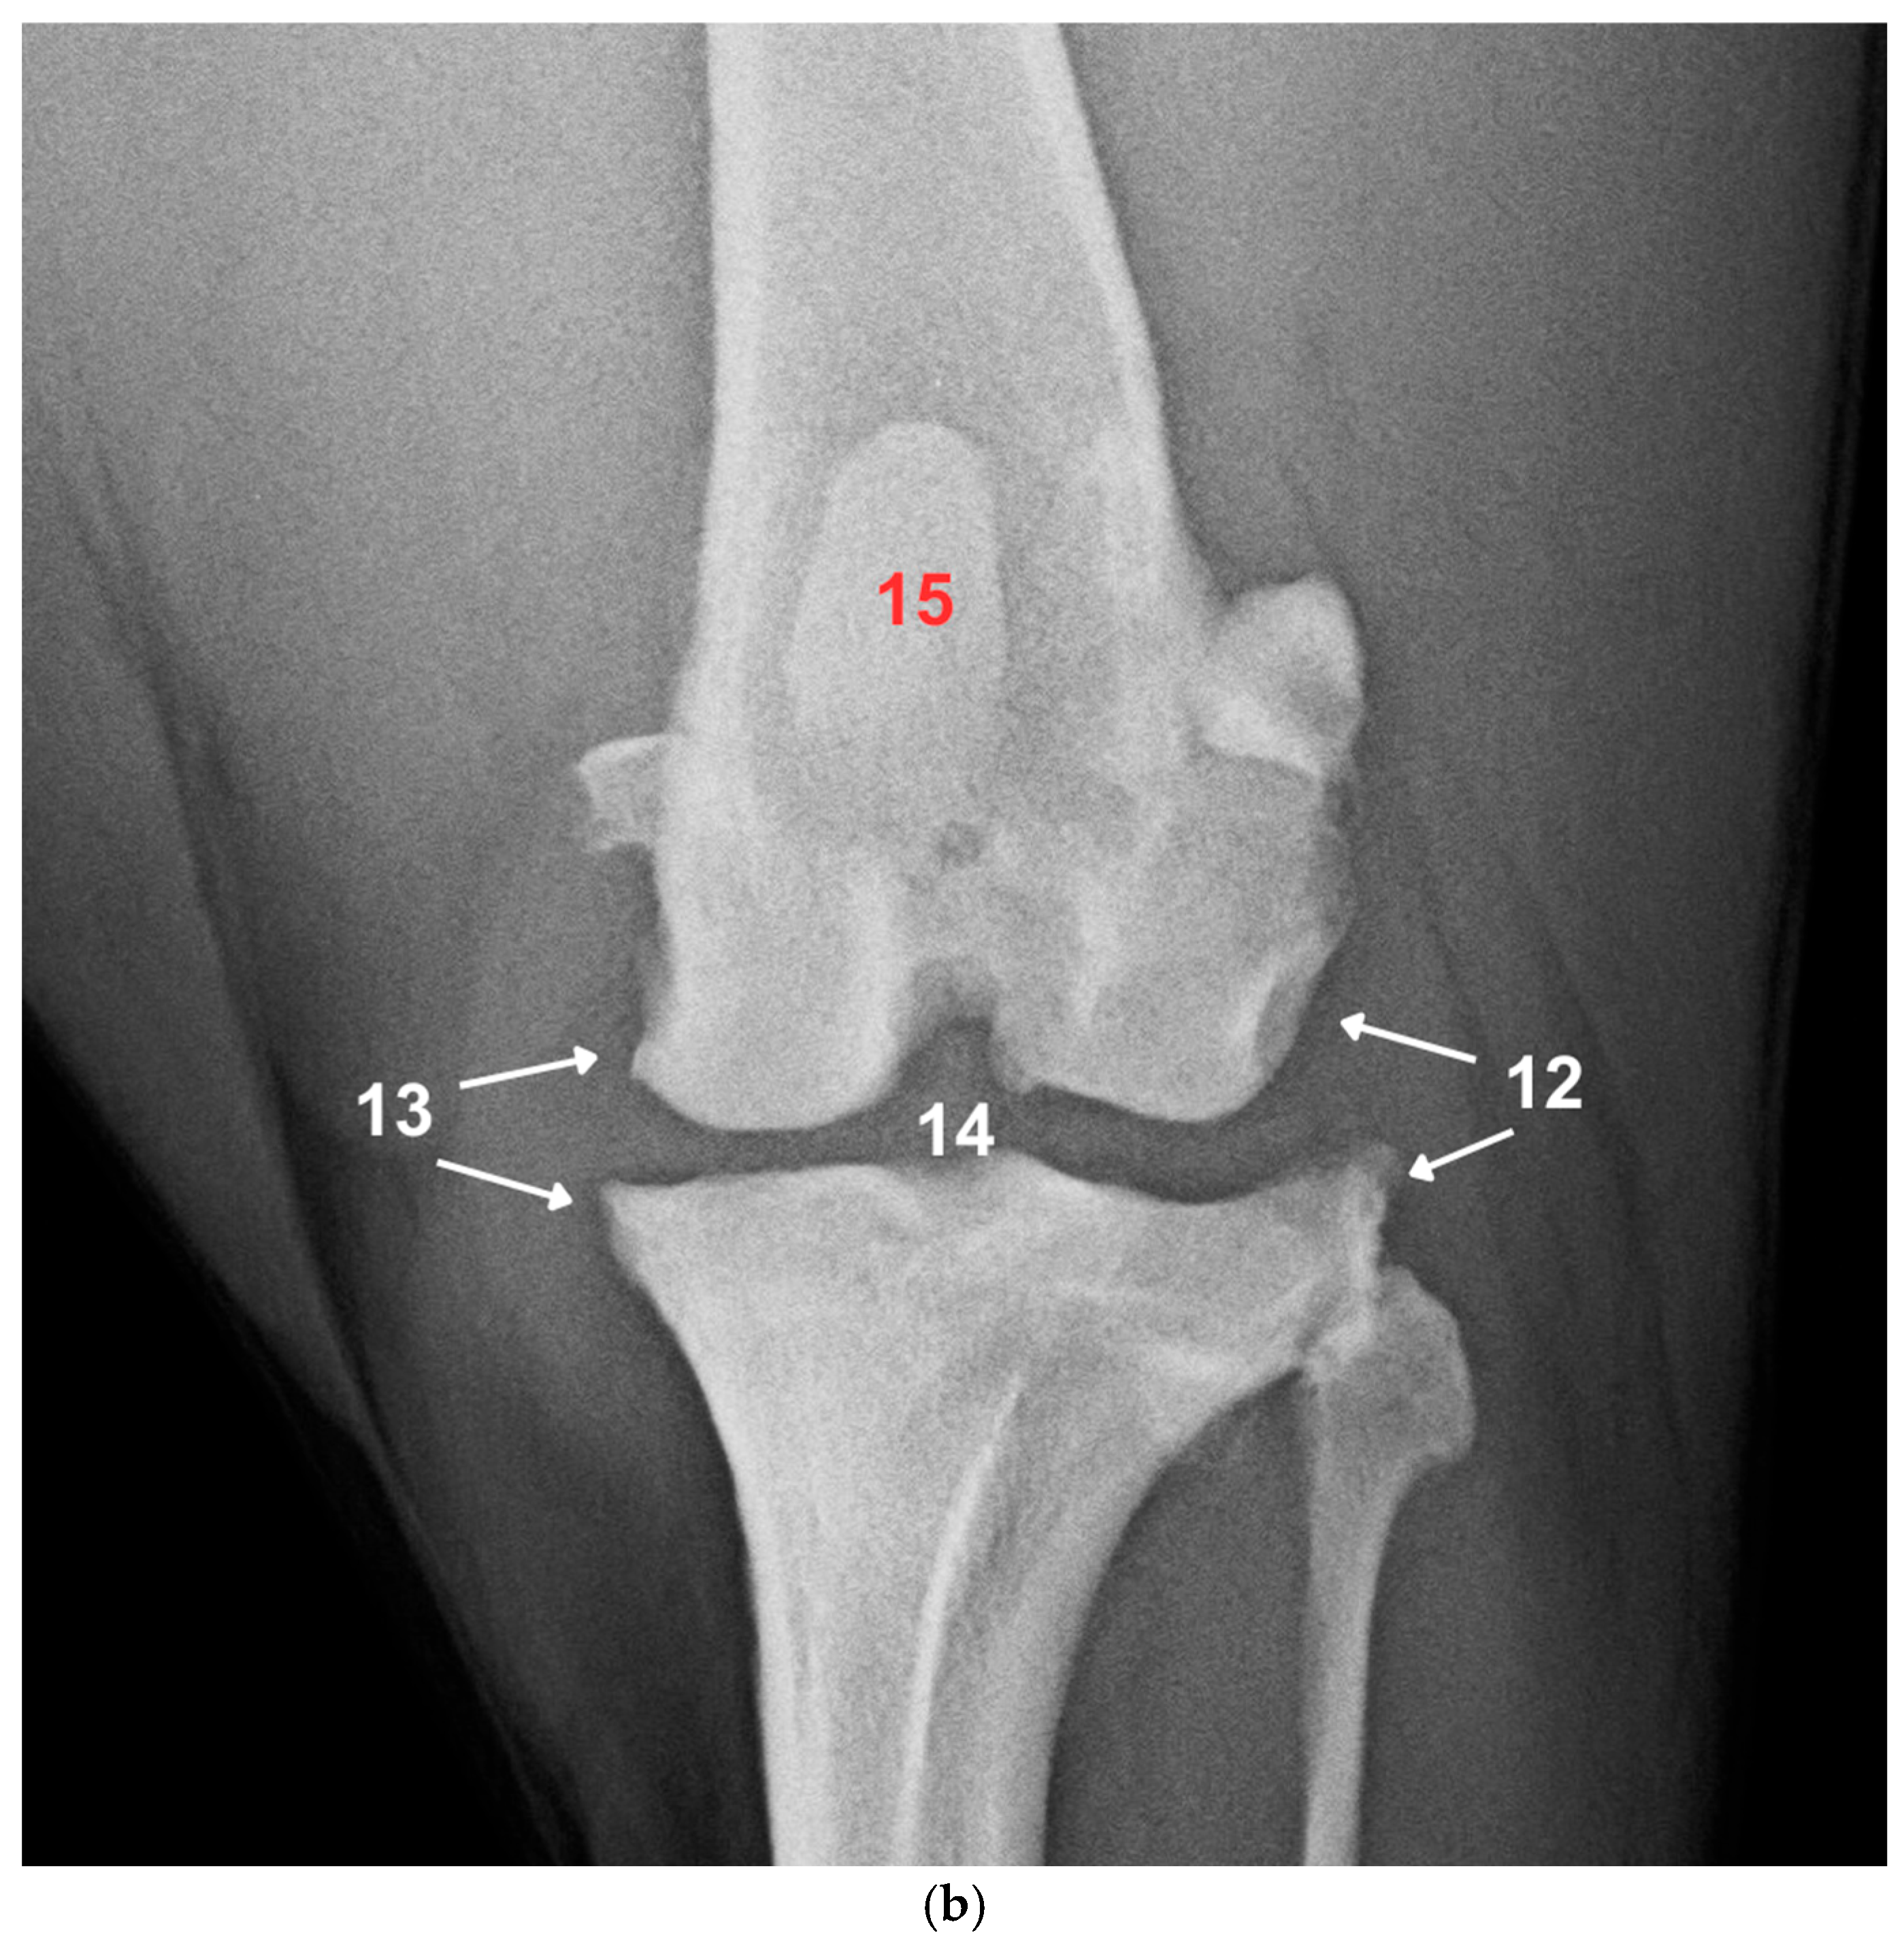

2.3. Radiographic Examination and Scoring

| Grade | Severity | Changes |

|---|---|---|

| 1 | No radiological signs of osteoarthritic changes | No osteophytes/enthesophytes detectable at bone points. The bone contour corresponds to normal anatomy. |

| 2 | Minor radiographic evidence of osteophytic changes | Osteophytes/enthesophytes are detectable but do not result in loss of distinctness of the bone contour. |

| 3 | Moderate radiographic evidence of osteoarthritic changes | Osteophytes/enthesophytes are clearly visible, and loss of bone contour may be present. |

| 4 | High-grade radiographic evidence of osteoarthritic changes | Osteophytes/enthesophytes extend well beyond the bone contour and may be associated with significant loss of distinctness of the bone contour. |